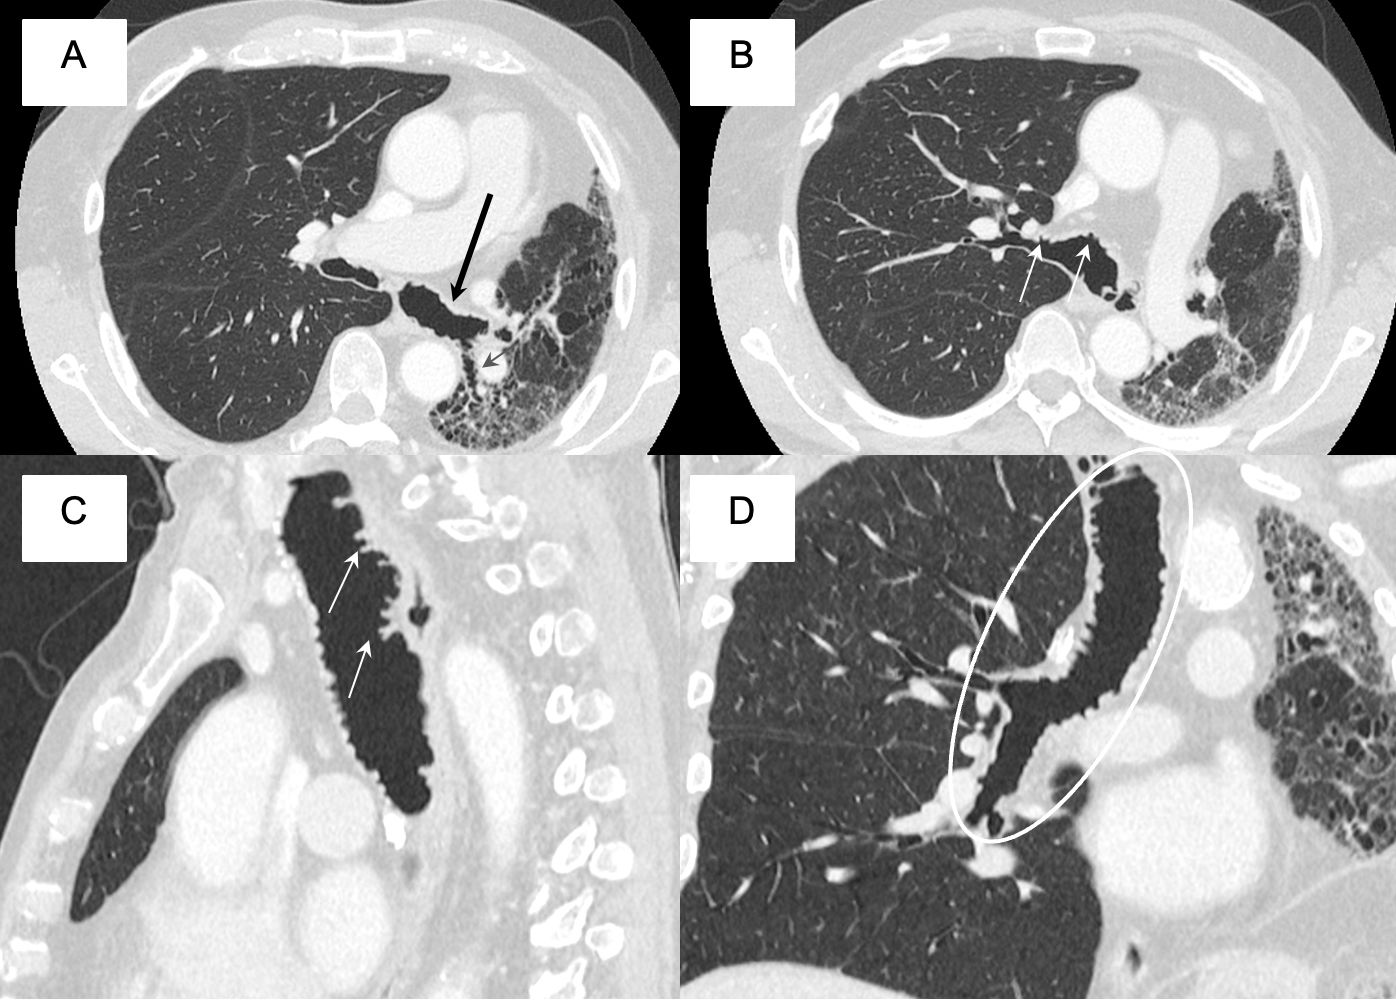

We present the case of a 72-year-old patient with a history of right lung transplantation (February 2018) treated with tacrolimus and rapamycin, who in October 2024 presented deterioration of lung function. A thoracic CT scan was performed in which tracheobronchial involvement was observed, with irregularity of the posterior wall of the trachea and bronchi, and formation of saccular dilations and tracheal pseudomembranes (Fig. 1). All this suggested a pseudomembranous tracheobronchitis secondary to subacute fungal infection. A bronchoscopy confirmed the presence of Aspergillus terreus, and treatment with isavuconazole and inhaled voriconazole was administered. Pseudomembranous tracheobronchitis is a condition in which pseudomembranes form in the trachea and bronchi, obstructing the airways and making it difficult to breathe. Its etiology can be bacterial, fungal, or related to connective tissue diseases. Chest CT scans show thickening of the tracheal and bronchial walls (Fig. 1), pseudomembranes (Fig. 1), airway obstruction, and pulmonary involvement such as atelectasis or consolidation [1]. Treatment is based on identifying the cause and giving appropriate treatment [2–4].

(A, B) CT scan showing formation of saccular dilations and tracheal pseudomembranes on the trachea and main bronchi (black and white arrows). (C) CT scan in a sagittal view showing affectation of the anterior and posterior walls of the trachea (white arrows). (D) MPR reconstruction of the trachea and right main bronchus showing an extensive mural disease (white ellipse).